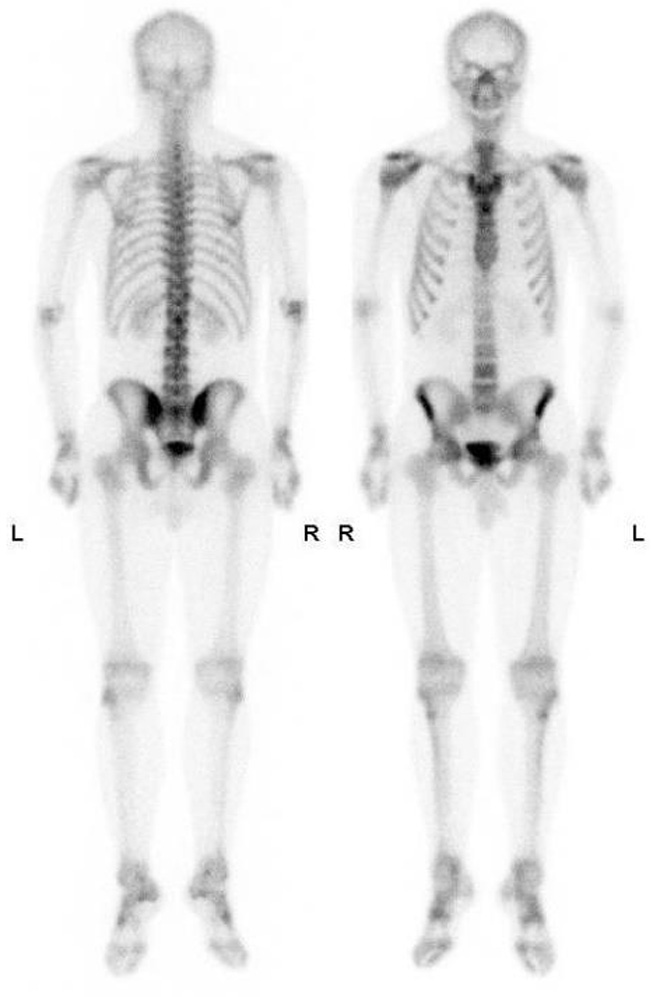

Bone Scans

Advantages of Bone scans over Conventional Imaging:

Early detection of bone metabolism changes, whole body screening

3 Phase Bone Scan: blood flow, blood pool, delayed.

Used for: osteomyelitis, prosthesis infection

SPECT/CT Benefits

SPECT: a nuclear medicine imaging technique that creates detailed, 3D images of organs, tissues, and bones by detecting the gamma rays emitted by radioactive tracers injected into the body

Benefits:

Combines function and structure so improved localisation

Superscan

Intense skeletal uptake with reduced renal/ST activity (eg: metastatic disease)

Common Indications:

? bony mets

Infection

Trauma

Arthritis